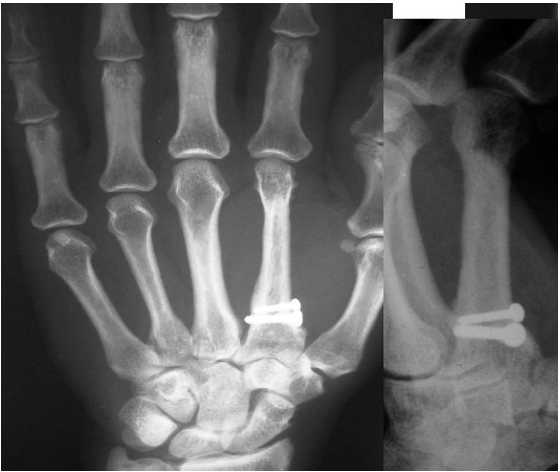

Radiograph showed an expansile lesion involving the distal half of the index finger metacarpal extending to the articular surface. Cortex of the bone was thinned but not broken. There was no calcification inside the lesion (figure 2). Blood investigations like serum calcium, phosphorous, alkaline phosphatase, and parathyroid hormone levels, and other blood parameters were within the normal range.

Figure 2. Preoperative radiograph of case 1 showing expansile lesion of index metacarpal.

Distal 2/3rd of the index finger metacarpal was excised,

Free grafting of the 3rd metatarsal from the left foot was performed (figure 3) The graft had incorporated in four months (figure 4).

Figure 4. Follow up radiograph at nine years (case 1).